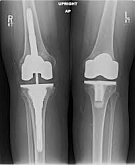

Еndoprosthesis of knee joint

In the late stages of arthrosis of the knee joint, accompanied by a pronounced restriction of the volume of movements, constant intense pain, deformity of the limb, the only way to recover is to replace the affected joint with an artificial joint - arthroplasty.

This method allows you to return the correct form of the limb, the full volume of movements in the joint, relieve the constant pain and crunch during movements and, as a result, significantly improve the patient's quality of life.

Below are presented X-ray photographs and photographs, illustrating the amount of motion in the affected joint before and after surgery.